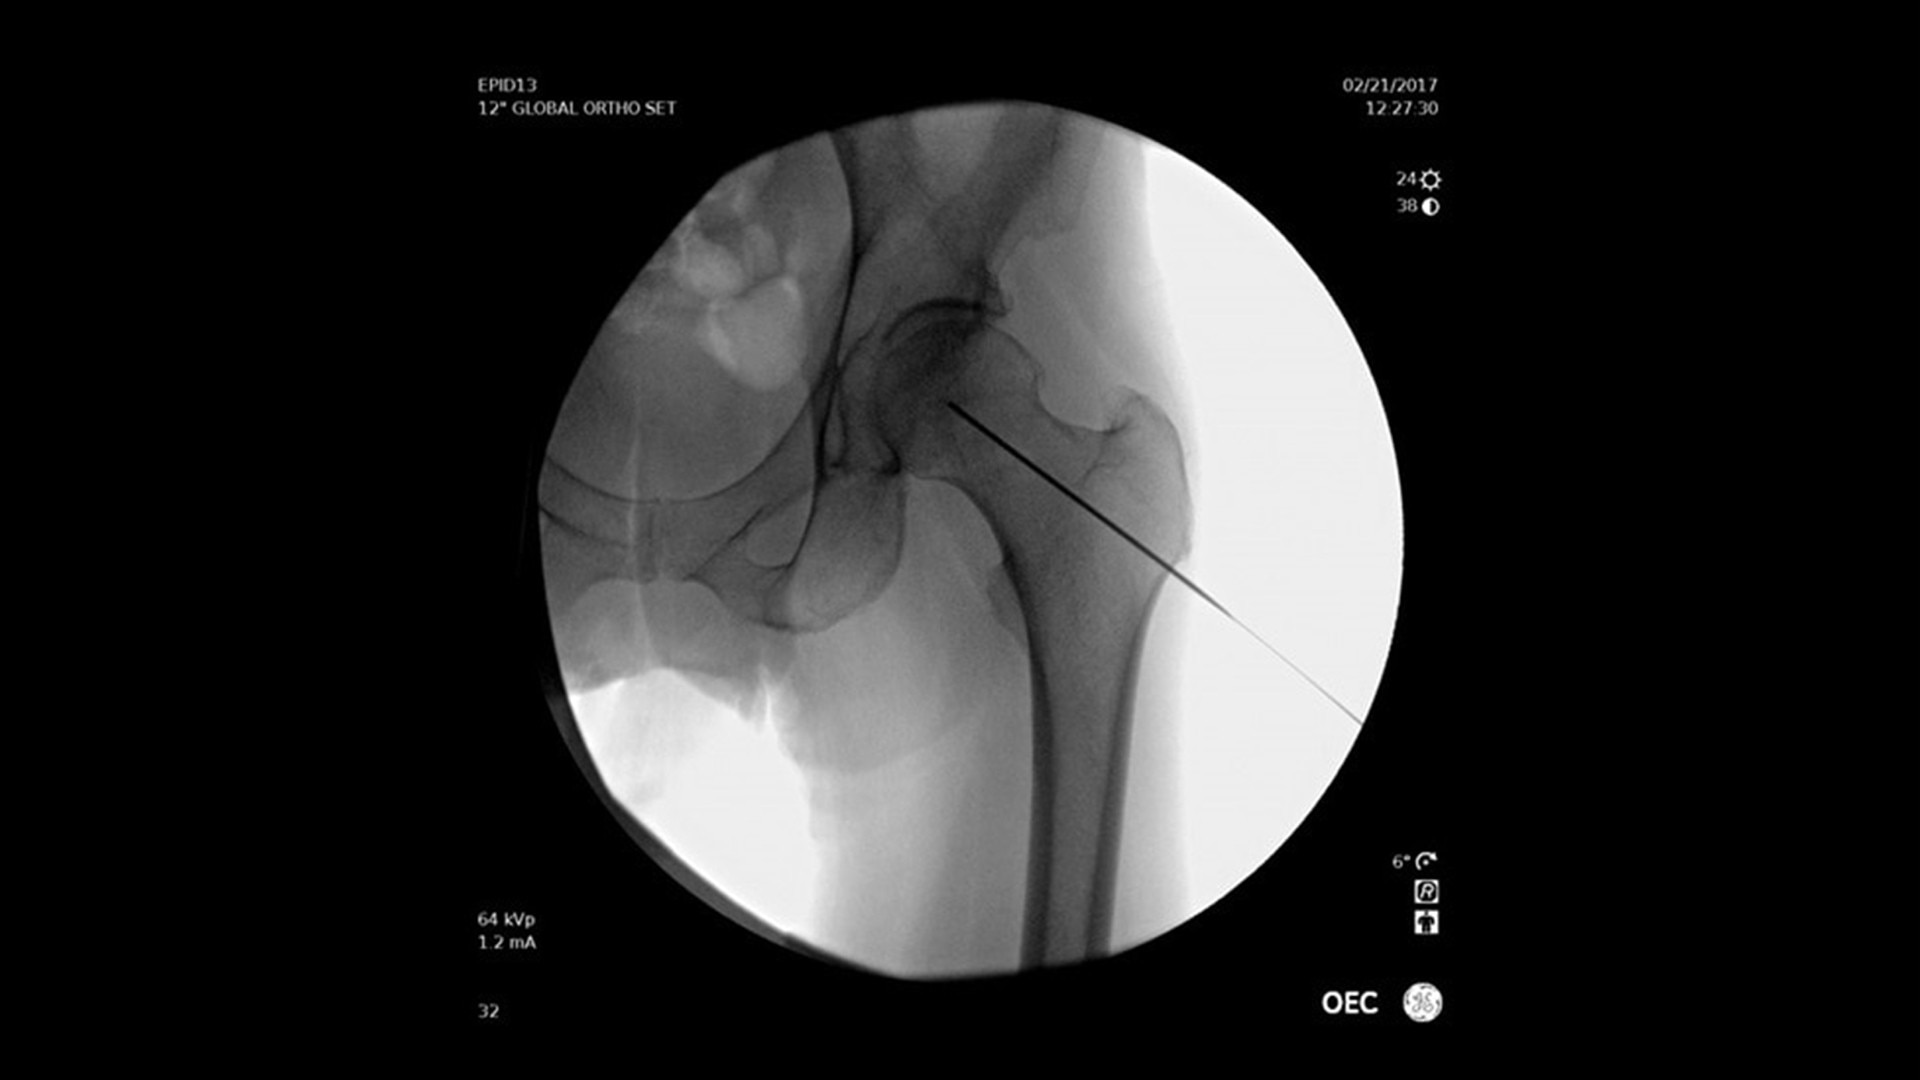

Vielseitig einsetzbar – ideal für orthopädische, gastrointestinale, endoskopische, urologische, neurologische und vaskuläre Eingriffe sowie für die Intensiv- und Notfallmedizin.

Der OEC Elite unterstützt Ihr OP-Team mit fortschrittlicher Bildverarbeitung, die sich dynamisch an klinische Anforderungen anpasst. So entstehen jederzeit präzise und detailreiche Bilder.

Renommierte Bildgebung – mehr sehen, mit weniger Dosis.

Nutzen Sie innovative Funktionen wie Live-Zoom, Digital Pen und vorkonfigurierte Bildprofile – darunter Pädiatrie, General HD und die optionale Bolus-Verfolgung – für eine präzise und schonende Bildgebung.

Im Vergleich zu herkömmlichen Monoblock-C-Bögen ermöglicht der OEC Elite eine bis zu 22 % größere Darstellung anatomischer Strukturen und eine nähere Positionierung des Detektors an der Patientenanatomie.

Das ergonomische Design ermöglicht eine einfache Positionierung des Detektors rund um den OP-Tisch – ideal für schwer zugängliche Winkel und niedrige Tischhöhen.